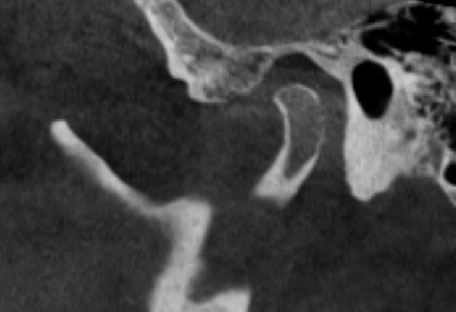

После 6 мес. лечения пациенту провели оценку положения головок нижней челюсти с каппой по данным КТ (рис. 6, 7).

Рис. 6. Правый височно-нижнечелюстной сустав после лечения с каппой

Fig. 6. Right temporomandibular joint after using the splint

Рис. 7. Левый височно-нижнечелюстной сустав после лечения с каппой

Fig. 7. Left temporomandibular joint after using the splint